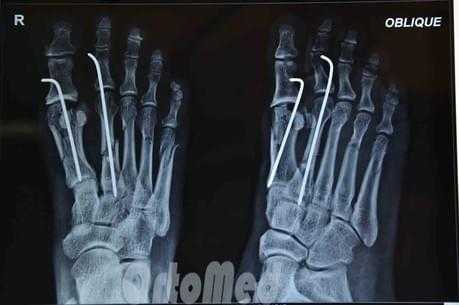

• Фиксация спицами при выраженном смещении отломков

Чрескожная фиксация спицами

Была популярна на протяжении многих лет и продолжает оставаться одним из самых популярных методов в международном масштабе.

Сначала врач закрыто устраняет смещение отломков, затем через отломки в определенных (учитывая характер перелома) направлениях просверливаются спицы.

Плюсы: малая травматичность, быстрота, легкость, дешевизна, отсутствие разреза и как следствие послеоперационного рубца.

Минусы: концы спиц остаются над кожей, для того чтобы спицу можно было удалить после срастания перелома; риск инфицирования раны и проникновение инфекции в область перелома; длительное ношение гипсовой повязки 1 месяц; неудобства в повседневной жизни.